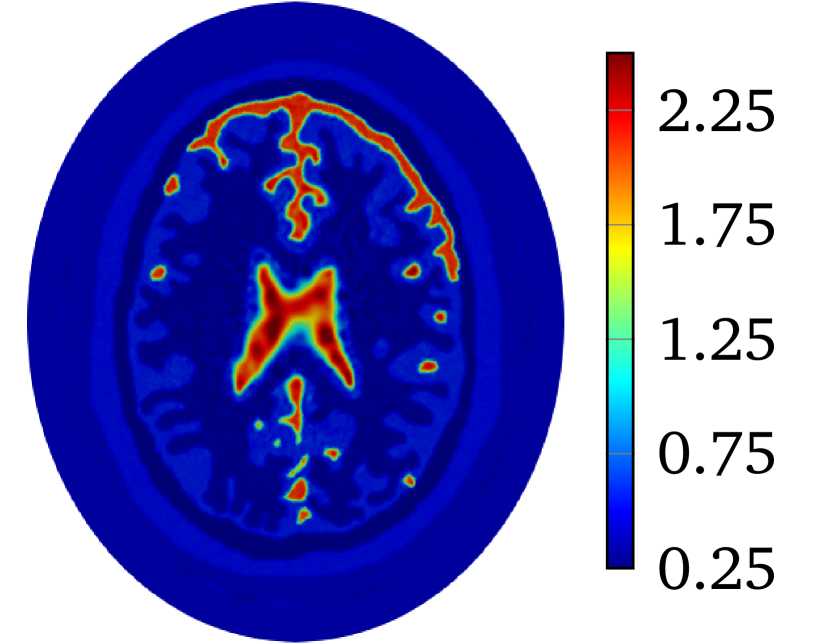

Though LM-SCEM performs well for reconstructing the conductivity map, its efficiency of the computation decreases quickly with the increase of measurements. Since EIT is not very sensitive to the change of interior conductivity, the electrical potential should converge faster than the convergence of the conductivity. The human-brain model is used here for numerical experiments with LM-SCEM. The elliptic domain is characterized with 8 cmtimes8cm8\text{\,}\mathrm{c}\mathrm{m} major and 9 cmtimes9cm9\text{\,}\mathrm{c}\mathrm{m} minor axes, and the domain is meshed with 36893 triangular elements. The parameters are given as α0=150subscript𝛼0150\alpha_{0}=150, a=2.0𝑎2.0a=2.0 and β=1×103𝛽1E-3\beta=$1\text{\times}{10}^{-3}$. The current patterns I(2)superscript𝐼2I^{(2)} and I(3)superscript𝐼3I^{(3)} are used in the reconstruction. With 60 dBtimes60dB60\text{\,}\mathrm{d}\mathrm{B} noise, the iteration is terminated when τL2<1×104subscriptnorm𝜏superscript𝐿21E-4\|\tau\|_{L^{2}}<$1\text{\times}{10}^{-4}$ or the maximum number of iterations equals 30. The reconstruction based on LM-SCEM is shown in Figure 7(a). 𝒰superscript𝒰\mathbfcal{U}^{k} of each current pattern is computed with SCEM and σksubscript𝜎𝑘\sigma_{k} for k𝑘k-th iteration, ηbsuperscript𝜂𝑏\eta^{b} easily follows then. The variation of the relative error η𝜂\eta and ηbsuperscript𝜂𝑏\eta^{b} are shown in Figure 6(a) and Figure 6(b), respectively. As can be seen, η𝜂\eta slowly converges to 4.09%percent4.094.09\%. This error is much larger than the input noise level, this is mainly caused by the complexity of the phantom and the high contrast of σ𝜎\sigma among different tissues. But the potentials on the boundary for both I(2)superscript𝐼2I^{(2)} and I(3)superscript𝐼3I^{(3)} converge fast to a level of ηb<1×104superscript𝜂𝑏1E-4\eta^{b}<$1\text{\times}{10}^{-4}$ in few iterations. Therefore, the boundary potential converges much faster. This property is exploited here to accelerate the computation by mixing LM-SCEM and LM-DCM, as demonstrated in Algorithm 2. In this computation, the LM-SCEM is stoped when ηbsuperscript𝜂𝑏\eta^{b} for all current patterns are smaller than 1×1031E-31\text{\times}{10}^{-3}. The LM-DCM is performed in the region Ω={x|xΩ,dist(x,Ω)>5 mm}superscriptΩconditional-set𝑥formulae-sequence𝑥Ω𝑑𝑖𝑠𝑡𝑥Ωtimes5mm\Omega^{\prime}=\{x\ |\ x\in\Omega,\ dist(x,\partial\Omega)>$5\text{\,}\mathrm{m}\mathrm{m}$\} with δd=5 mmsubscript𝛿𝑑times5mm\delta_{d}=$5\text{\,}\mathrm{m}\mathrm{m}$. The potential on ΩsuperscriptΩ\partial\Omega^{\prime} is computed with SCEM and the reconstructed σ𝜎\sigma from LM-SCEM. The power density in ΩsuperscriptΩ\Omega^{\prime} can be reconstructed with the method introduced by Ammari et al [4]. However, it requires the knowledge on the deformation caused by the ultrasonic waves, therefore, we compute it with DCM instead. Noise with SNR=60 dBabsenttimes60dB=$60\text{\,}\mathrm{d}\mathrm{B}$ is added, and LM-DCM is used for the reconstruction. The relative error η𝜂\eta is given in Figure 6(a). The conductivity map is reconstructed with η=8.13×104𝜂8.13E-4\eta=$8.13\text{\times}{10}^{-4}$ in 30 iterations, and the result is given in Figure 7(b). Here, the time required for 30 LM-DCM iterations is about 20 minutes which is approximately the time needed for one LM-SCEM iteration. So the reconstruction efficiency is greatly improved, and better results are obtained. A similar computation with 40 dBtimes40dB40\text{\,}\mathrm{d}\mathrm{B} noise is further considered here. As seen in Figure 6(b), increasing noise does not influence much the convergence of the boundary potential, therefore, this mixed approach can be a good way to remove noise from the measured power density. With 40dB noise in the reconstructed power density in ΩsuperscriptΩ\Omega^{\prime}, the distribution of σ𝜎\sigma obtained with LM-DCM is shown in Figure 7(d). Comparing it to the results obtained with LM-SCEM, as shown in Figure 7(c), a better noise tolerance is observed in LM-DCM.

Refer to caption

(a) LM-SCEM, SNR = 60 dBtimes60dB60\text{\,}\mathrm{d}\mathrm{B}

(b) Mixed, SNR = 60 dBtimes60dB60\text{\,}\mathrm{d}\mathrm{B}

(c) LM-SCEM, SNR = 40 dBtimes40dB40\text{\,}\mathrm{d}\mathrm{B}

(d) Mixed, SNR = 40 dBtimes40dB40\text{\,}\mathrm{d}\mathrm{B}

Figure 7: The conductivity map of human-brain model reconstructed with current pattern I(2)superscript𝐼2I^{(2)} and I(3)superscript𝐼3I^{(3)}. The reconstruction with only LM-SCEM are given in (a) and (c) for 60 dBtimes60dB60\text{\,}\mathrm{d}\mathrm{B} and 40 dBtimes40dB40\text{\,}\mathrm{d}\mathrm{B} noises. Corresponding reconstructions by mixing LM-SCEM and LM-DCM are given in (b) and (d).